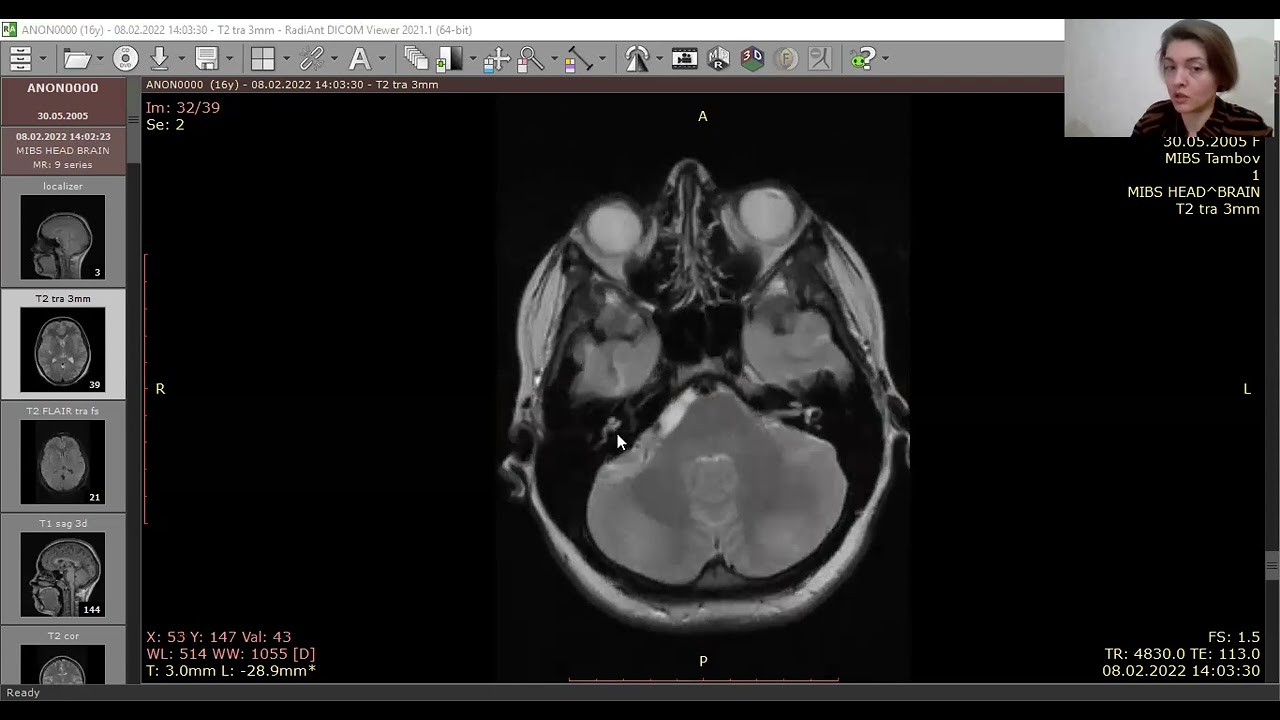

Субтенториальная эпидермоидная киста и арахноидальная киста полюса левой височной доли. КТ, аксиальный срез (а), МРТ, аксиальное Т2-ВИ (b) и аксиальное Т1-ВИ (с) после введения КС. Ни КТ, ни традиционные МР-изображения не позволяют четко дифференцировать эпиде моидные кисты от арахноидальных. Подобно кисте паутинной оболочки, эпидермоидная киста выглядит гиподенсной (а) или гиперинтенсивной (b) и гипоинтенсивной по отношению к паренхиме головного мозга (с) и не накапливает КС (с, стрелка). Однако МР-сигнал в эпидермоидной кисте неоднородный.

Что покажут снимки МРТ головного мозга при эпидермоидной кисте

- Опухоли, обычно изоинтенсивные жидкости на Т2-ВИ и Т1-ВИ

- На FLAIR-изображениях содержимое опухоли выглядит гиперинтенсивным

- На диффузионно-взвешенных изображениях определяется значительное снижение диффузии.

- Характерные признаки- выраженное ограничение диффузии.